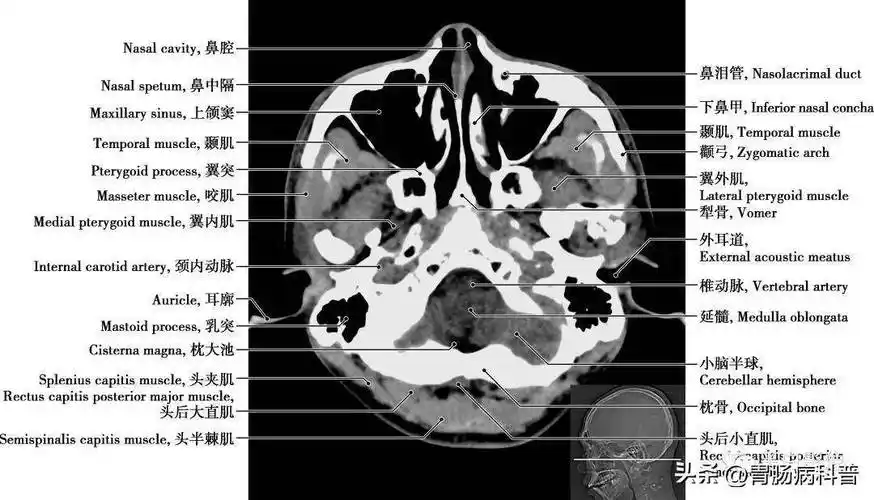

详细标注版——颅脑ct正常解剖图谱_中央_小脑_纤维